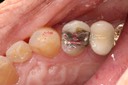

Wayne Chin #2 pre-op

Wayne Chin #2 prep